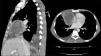

A 51-year-old man, former smoker with a history of hepatitis C infection, presented with symptoms of fever, arthralgia, and weight loss. After case history and physical examination were completed, which were unremarkable, additional tests were requested: complete blood count, serum biochemistry, viral serologies, autoimmunity, Mantoux and blood cultures. Of note was C-reactive protein 238mg/l. Imaging studies were performed, and a chest radiograph revealed a picture of water density in the right hilum and the chest computed tomography (CT) showed an anterior mediastinal mass 9×7cm consistent with infected embryonic remnants (Fig. 1). The patient was diagnosed with an infected pleuropericardial cyst, and antibiotic treatment began. Progress was good so the patient was discharged and scheduled for surgical extraction of the cyst.